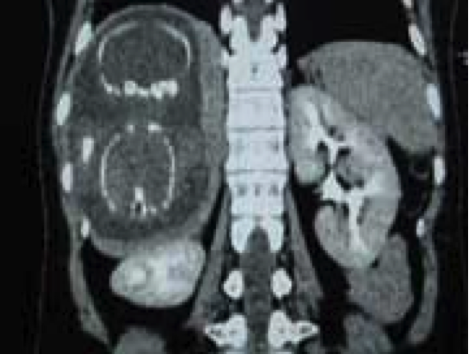

Bệnh nhân Lê Thị L. 27 tuổi, sống tại Rạch Giá được Bệnh viện đa khoa Kiên Giang chuyển đến Bệnh viện Từ Dũ lúc 23 giờ 30 phút ngày 27/08/2007; đã sinh 1 lần tại Bệnh viện Từ Dũ vào năm 2001. Trước nhập viện trên hai tháng, ngày 13/06, bệnh nhân đã được Bệnh viện đa khoa Kiên Giang mổ TNTC, cắt vòi tử cung phải; về nhà vẫn đau bụng âm ỉ, nhưng không đến khám lại. Từ ngày 20/08, bệnh nhân đau bụng âm ỉ vùng hạ sườn phải, siêu âm phát hiện thai trong ổ bụng, chuyển Bệnh viện Từ Dũ.

Tại Bệnh viện Từ Dũ, siêu âm và chụp CT tại Trung tâm Medic, phát hiện một thai sống khoảng 22 tuần trong ổ bụng vùng dưới hoành phải (dưới gan phải). Kích thước khối thai là 12x15x17cm. Bánh nhau dày 47mm, xâm lấn gan phải và có mạch máu nuôi xuất phát từ động mạch gan phải. Chẩn đoán: thai dưới gan, chỉ định mổ lấy khối thai và tiên lượng cuộc mổ khó nên mời phẫu thuật viên Bệnh viện Chợ Rẫy kết hợp cùng mổ.

![]() |

Hình 5. Thai nằm dưới gan (ngôi ngược) |

Hình 6. Thai trong ổ bụng. Thai ngôi ngược, có hình ảnh giống như thai trong tử cung nhưng không rõ hình tử cung, khối thai nằm dưới gan nên thấy đầu các xương sườn (Nguồn: ảnh phim Medic) |

Mở bụng ngày 30/08, có khoảng 200mL máu đã chảy trong ổ bụng, bề mặt gan nhẵn bóng, nhưng có khối lùng nhùng ở phân thùy VI, VII, VIII bị mặt trước của gan che lấp. Khi vén bờ trước dưới của gan, phát hiện thai bên trong, các gai nhau ăn sâu vào nhu mô gan, bám vào đến 2/3 gan. Mở túi thai, hút nước ối, lấy ra một bé gái khoảng 600g đã chết. Cắt rốn lấy thai và để lại bánh nhau nhưng bánh nhau tự bong khỏi gan, làm chảy máu nhiều. Tuy nhiên, khi lấy khối thai ra, dù đã để lại bánh nhau nhưng do bánh nhau tự bong ra và chảy máu rất nhiều, các phẫu thuật viên buộc phải quyết định lấy bánh nhau và cắt một phần gan do nhau bám vào đó. Đây là một kỹ thuật rất phức tạp và cầm máu vô cùng khó khăn. Các bác sĩ đã thực hiện buộc các mạch máu từ cuống gan, chèn gạc để cầm máu trong và truyền 8 đơn vị máu và huyết tương nhưng vẫn không thể kiểm soát được. Khoảng 15 phút sau, máu vẫn chảy nhiều ở diện gân đã cắt và bệnh nhân ngừng tim. Chẩn đoán phẫu thuật: thai dưới gan và tử vong do chảy máu. Nguyên nhân tử vong: chảy máu không cầm được.